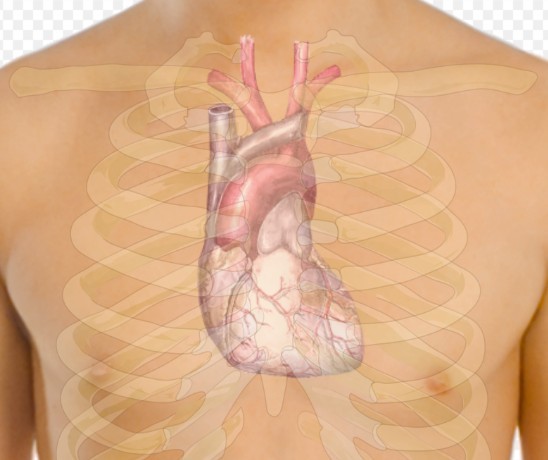

Шведские ученые из Каролинского института и Стокгольмского университета предупредили, что применение препаратов, усиливающих потенцию (PDE5i), таких как виагра, совместно с нитратами у мужчин со стабильной ишемической болезнью сердца, может значительно повысить риск смерти и сердечно-сосудистых осложнений.

Исследование, опубликованное в "Журнале Американского колледжа кардиологов" (JACC), включало в себя данные о 55 777 мужчинах, принимавших нитраты, из которых 5710 также использовали PDE5i. Результаты указывают на увеличение общей смертности и риска сердечно-сосудистых событий при совместном применении этих препаратов. Исследователи подчеркивают важность осторожного подхода к назначению PDE5i пациентам с сердечно-сосудистыми заболеваниями, особенно тем, кто принимает нитратные препараты, и рекомендуют обсудить с врачом потенциальные риски и выгоды такого лечения, сообщает Planet Today.